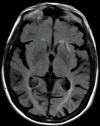

Neurodegenerative diseases are a devastating group of disorders that can be difficult to accurately diagnose. Although these disorders are difficult to manage owing to relatively limited treatment options, an early and correct diagnosis can help with managing symptoms and coping with the later stages of these disease processes. Both anatomic structural imaging and physiologic molecular imaging have evolved to a state in which these neurodegenerative processes can be identified relatively early with high accuracy. To determine the underlying disease, the radiologist should understand the different distributions and pathophysiologic processes involved. High-spatial-resolution MRI allows detection of subtle morphologic changes, as well as potential complications and alternate diagnoses, while molecular imaging allows visualization of altered function or abnormal increased or decreased concentration of disease-specific markers. These methodologies are complementary. Appropriate workup and interpretation of diagnostic studies require an integrated, multimodality, multidisciplinary approach. This article reviews the protocols and findings at MRI and nuclear medicine imaging, including with the use of flurodeoxyglucose, amyloid tracers, and dopaminergic transporter imaging (ioflupane). The pathophysiology of some of the major neurodegenerative processes and their clinical presentations are also reviewed; this information is critical to understand how these imaging modalities work, and it aids in the integration of clinical data to help synthesize a final diagnosis. Radiologists and nuclear medicine physicians aiming to include the evaluation of neurodegenerative diseases in their practice should be aware of and familiar with the multiple imaging modalities available and how using these modalities is essential in the multidisciplinary management of patients with neurodegenerative diseases.©RSNA, 2020.